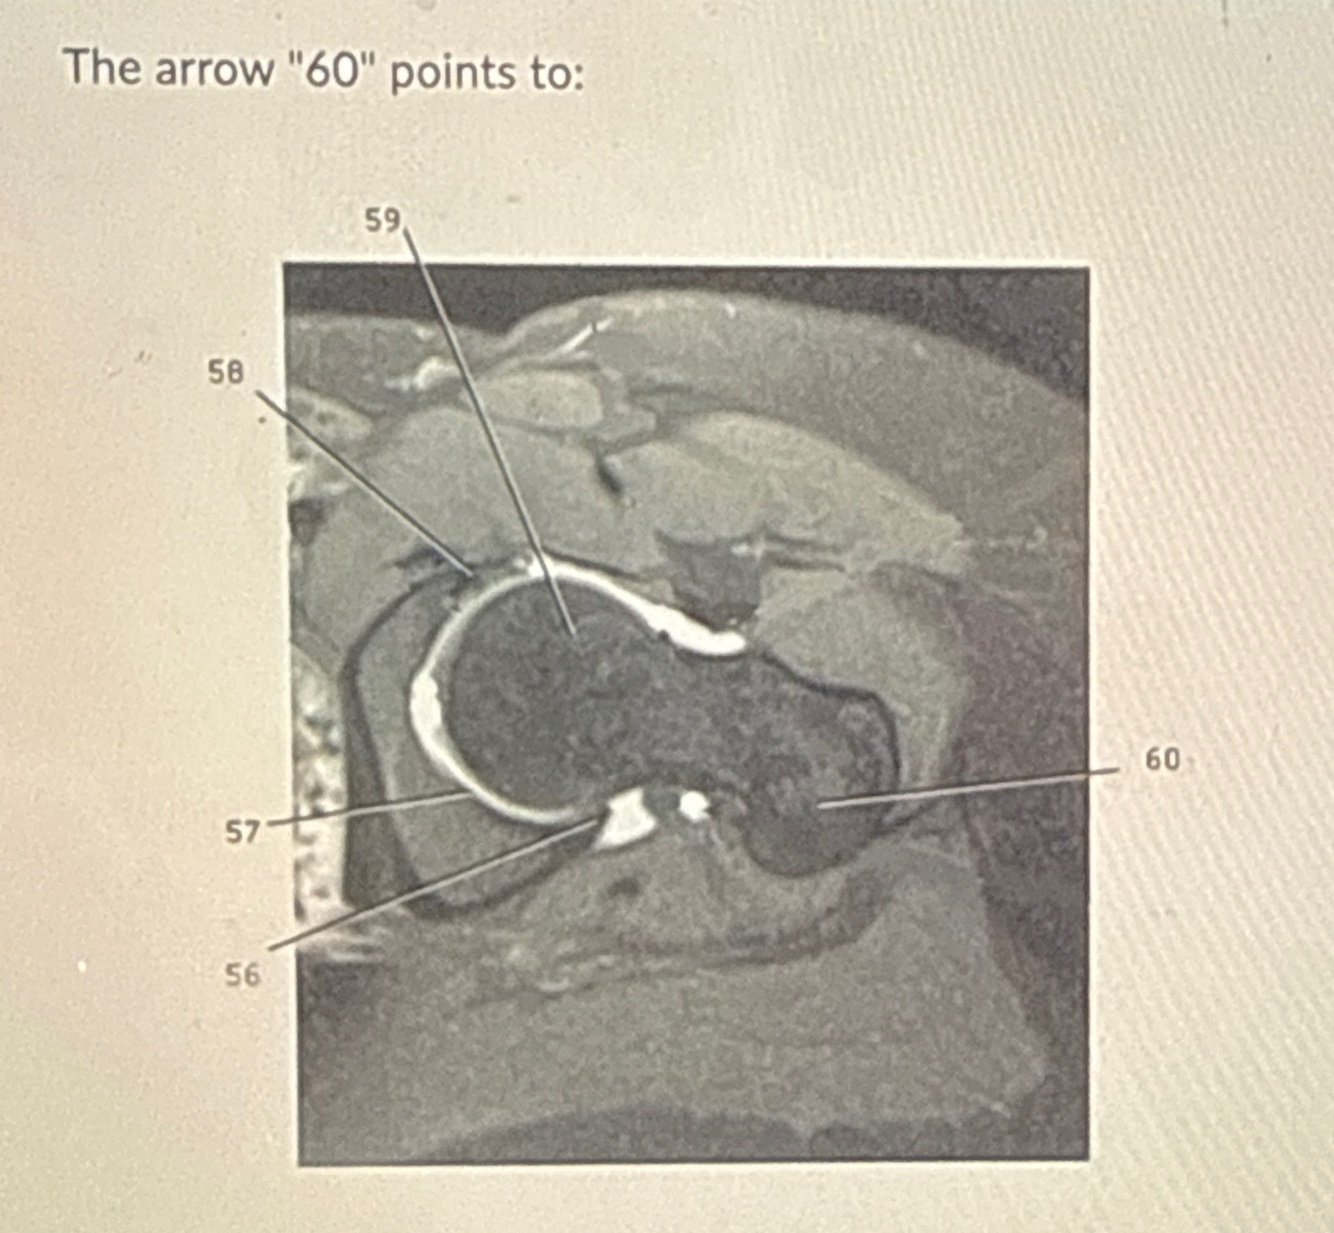

6

Q

A

ACL